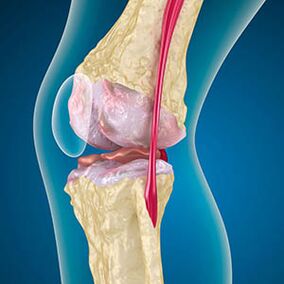

Knee joint arthrosis combines two processes: cartilage destruction and osteophyte growth or bone spur.The stage of the process is determined by the radiography.Arthrosis is believed to be the destruction of knee joints with age, the natural process of aging.The causes are muscle weakening and bad blood supply to the tissue.How to treat it without surgery?Eliminate factors that reduced muscle tone.

With arthrosis, the cartilage lining the bones is abrasion or completely absent.Damaged tissue is not a source of pain because it has no receptors.Inflammation in nearby structures causes characteristic symptoms.

The body continues the regeneration of damaged tissues, but the cartilage grows unevenly.As a result, irregularities are formed that impair other elements of the joint.The nature of the osteophytes is explained by compensation for smooth joint cartilage.Another version indicates that the growth of "Spurs"It is associated with an attempt to stabilize the joint medially or lateral due to muscle weakening.